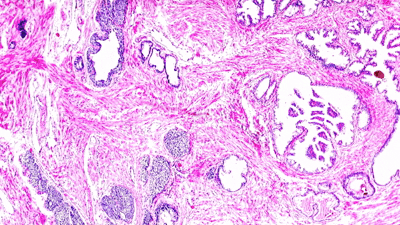

6. Histology Stains (e.g., H&E)

Stains such as hematoxylin and eosin (H&E) are indispensable for highlighting tissue structures. Other special stains (PAS, Masson’s trichrome, etc.) are used for specific diagnostic purposes. Quality stains ensure consistent coloration and interpretability.